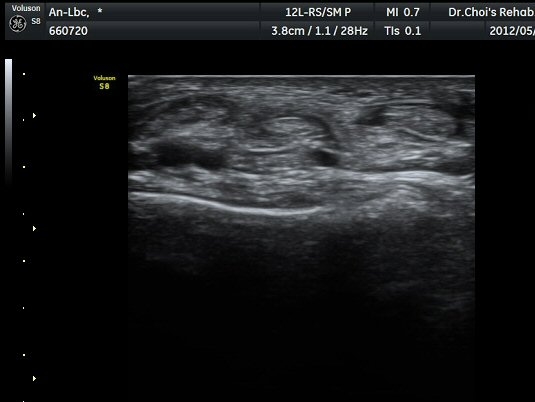

¹ß¸ñ ¾Õ Ⱦ´Ü¸é°Ë»ç¿¡¼­ Àü°æ°Ç(TA), ¾öÁö½ÅÀü°Ç(EPL), ¹ß°¡¶ô½ÅÀü°Ç(EDL)ÀÇ ºÎÁ¾ ¹×

°Ç ÁÖÀ§ ¼ö¾× Àú·ù°¡ °üÂûµÈ´Ù(»çÁø 1, 2). °ÇÀÇ ºñÈÄ¿Í ¼ö¾×Àú·ù´Â °ÇÃø(»çÁø 4)°ú ºñ±³Çϸé

¶Ñ·ÈÇÏ´Ù. Àü°æ°Ç Á¾´Ü¸é°Ë»ç¿¡¼­ °ÇÀÇ ºÎÁ¾°ú °Ç ÁÖÀ§ ¼ö¾× Àú·ù°¡ °üÂûµÈ´Ù(»çÁø 3). °ÇÀÇ